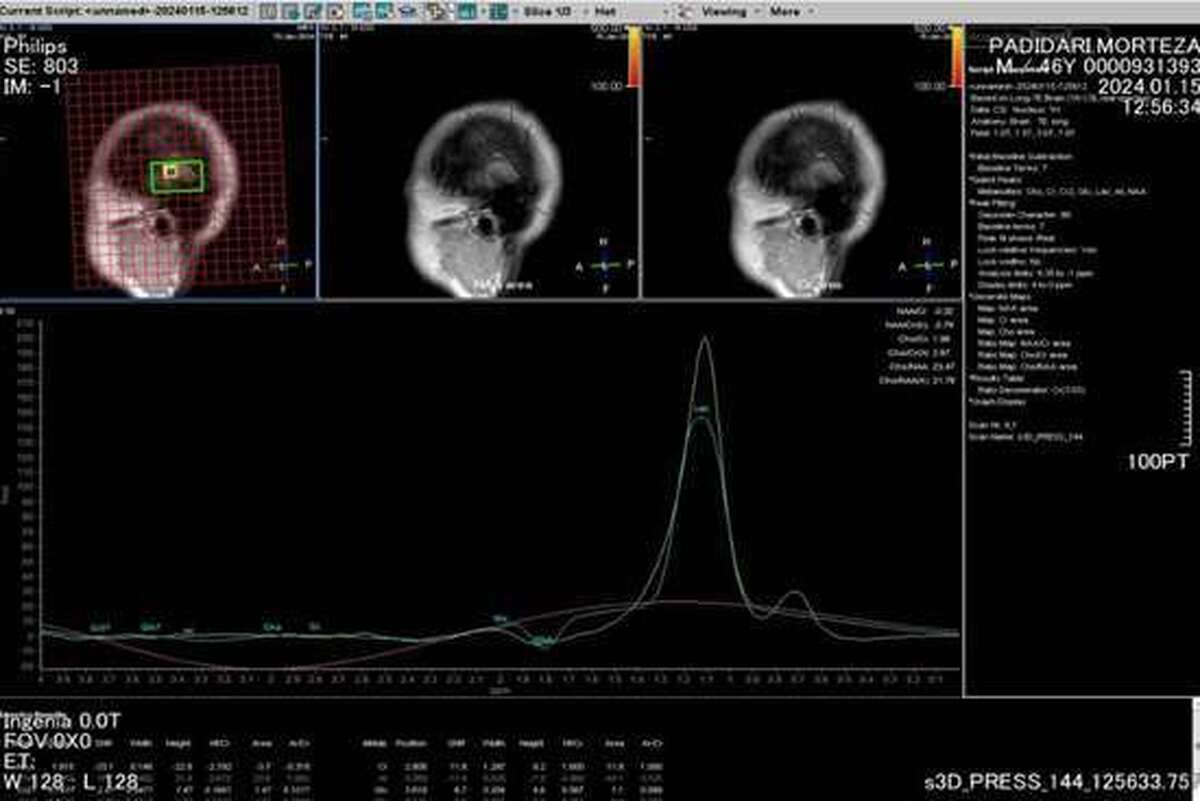

در این همکاری، API از مولکول وانادیوم اندوهدرال فولرن (V@C ۶۰) که توسط RC توسعه یافته و در ۱۱ ژوئن ۲۰۲۴ توسط ویجر معرفی شده بود، استفاده خواهد کرد. هدف این پروژه، فرمولاسیون چندین عامل کنتراست دهنده MRI نوآورانه است که از نظر ریلاکسویتی، حساسیت و عملکرد تصویربرداری مورد آزمایشهای دقیق قرار خواهند گرفت. در صورت موفقیت، این پروژه وارد فاز پیشبالینی خواهد شد.

به گزارش فایننس یاهو، تحقیقات ویجر نشان میدهد که عوامل کنتراست دهنده مبتنی بر V@C ۶۰ میتوانند مزایای کلیدی نسبت به عوامل کنتراست دهنده سنتی مبتنی بر گادولینیوم (GBCAs) ارائه دهند، از جمله:

افزایش وضوح تصویربرداری

کاهش سمیت و بهبود ایمنی بیمار

کاربردهای گستردهتر در حوزههای پزشکی

فولرنهای اندوهدرال به دلیل پایداری استثنایی، زیستدسترسی بالا و بهبود ویژگیهای تصویربرداری، یک پیشرفت انقلابی در نانوداروها محسوب میشوند. این ساختارها میتوانند با افزایش وضوح تصویر، کاهش سمیت و امکانپذیر کردن تشخیص و درمانهای هدفمند، دنیای تصویربرداری پزشکی را متحول کنند. توانایی RC در تولید این فولرنها در مقیاس صنعتی، نقطه عطف مهمی در فناوری تصویربرداری پزشکی و تحویل داروهای جدید خواهد بود.